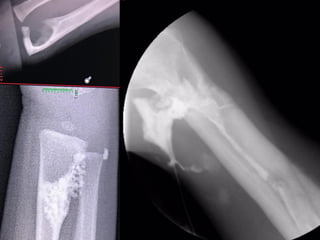

• Radiografías

• Laboratorios (BH completa, VSG,

PCR)

• Resonancia Magnética.

• Gammagrafía